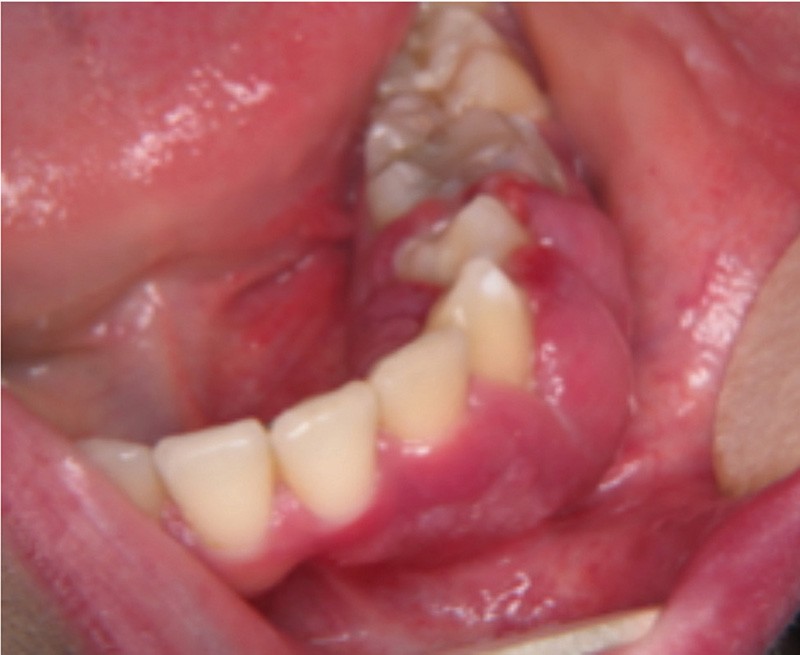

Examen clinique. Sous le maquillage, l’inspection exo-buccale révélait sur la joue gauche une lésion angiomateuse de couleur rouge. L’examen endo-buccal montrait un accroissement gingival violine qui s’étendait de 31 à 36. La palpation mettait en évidence une lésion légèrement molle, non pulsatile, saignant facilement.

Examen paraclinique. Une biopsie a été réalisée et l’examen anatomopathologique a révélé de nombreuses cavités vasculaires de taille variable dont la paroi mince était constituée d’un simple endothélium ; cet aspect est compatible avec celui d’une malformation veineuse.